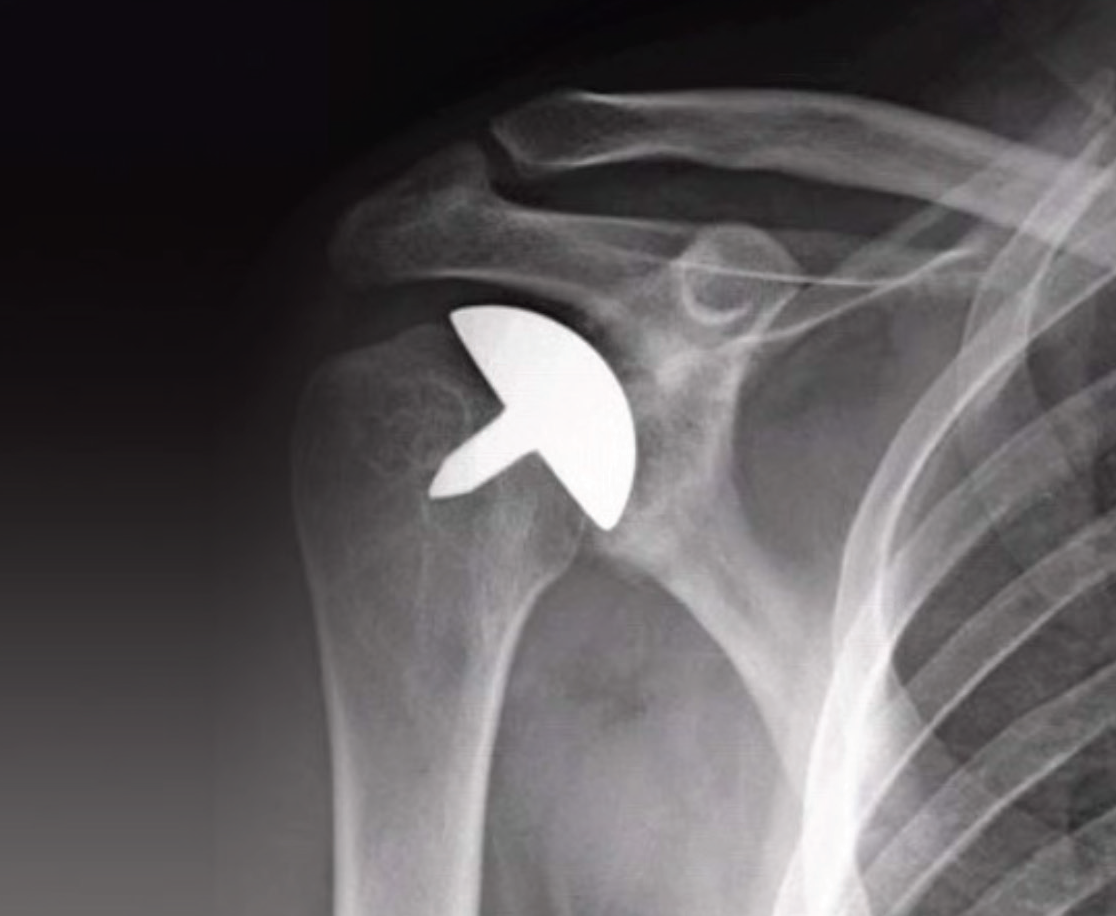

Yüzey Yenileme Artroplastisi: Yüzey yenileme hemiartroplastisi, humerus başının sadece eklem yüzeyinin sapsız, başlık benzeri bir protezle değiştirilmesini içerir. Kemik koruyucu avantajıyla omuz artriti olanlara standart saplı omuz protezine alternatif sunar. Glenoid hala sağlam bir kıkırdak yüzeyine sahipse, humerus boynunda veya başında yeni bir kırık yoksa ve omuz kemiğinin korunması gerekiyorsa bu ameliyat yapılır.

Yüzey artroplastisi. Burada sadece humerus başının eklem yüzü değiştirilir.

Genç veya çok aktif hastalarda total omuz protezlerinde meydana gelebilecek aşınma ve gevşeme risklerini ortadan kaldırır. Daha konservatif doğası nedeniyle, daha sonra gerekirse total omuz replasmanına dönüştürülmesi daha kolay olabilir. Dikkat edilecek husus, eklem uyumunun implant konulduktan sonra da devam ettirilmesidir.